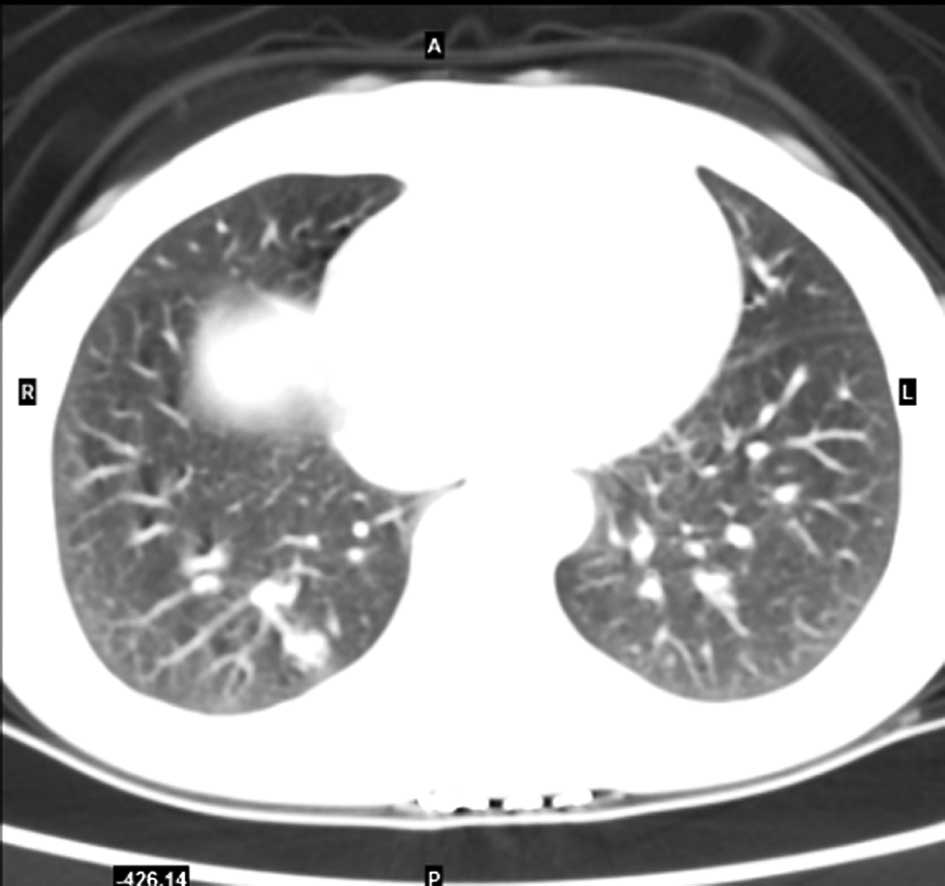

A case of pulmonary sclerosing hemangioma with low 18FDG uptake in PET

Pulmonary sclerosing hemangioma (PSH) is a relatively rare benign neoplasm, often asymptomatic and presenting as a solitary pulmonary nodule on radiological imaging studies. In the present case report, we examined a case of PSH in a young adult female, and reviewed the literature pertaining to PSH with an emphasis on 18F-fluorodeoxyglucose positron emission tomography/computed tomography (18FDG PET/‌CT) and pathology. Immunohistochemical staining was also performed to confirm the diagnosis of sclerosing hemangioma. The results revealed that the tumor cells were immunopositive for epithelial membrane antigen, thyroid transcription factor-1 and vimentin and cytoskeleton 7. The patient recovered and was discharged. Thus, 18FDG PET/CT may be used in the diagnosis of a solitary benign pulmonary nodule.

Figure 1

Figure 2

Figure 3

Figure 4